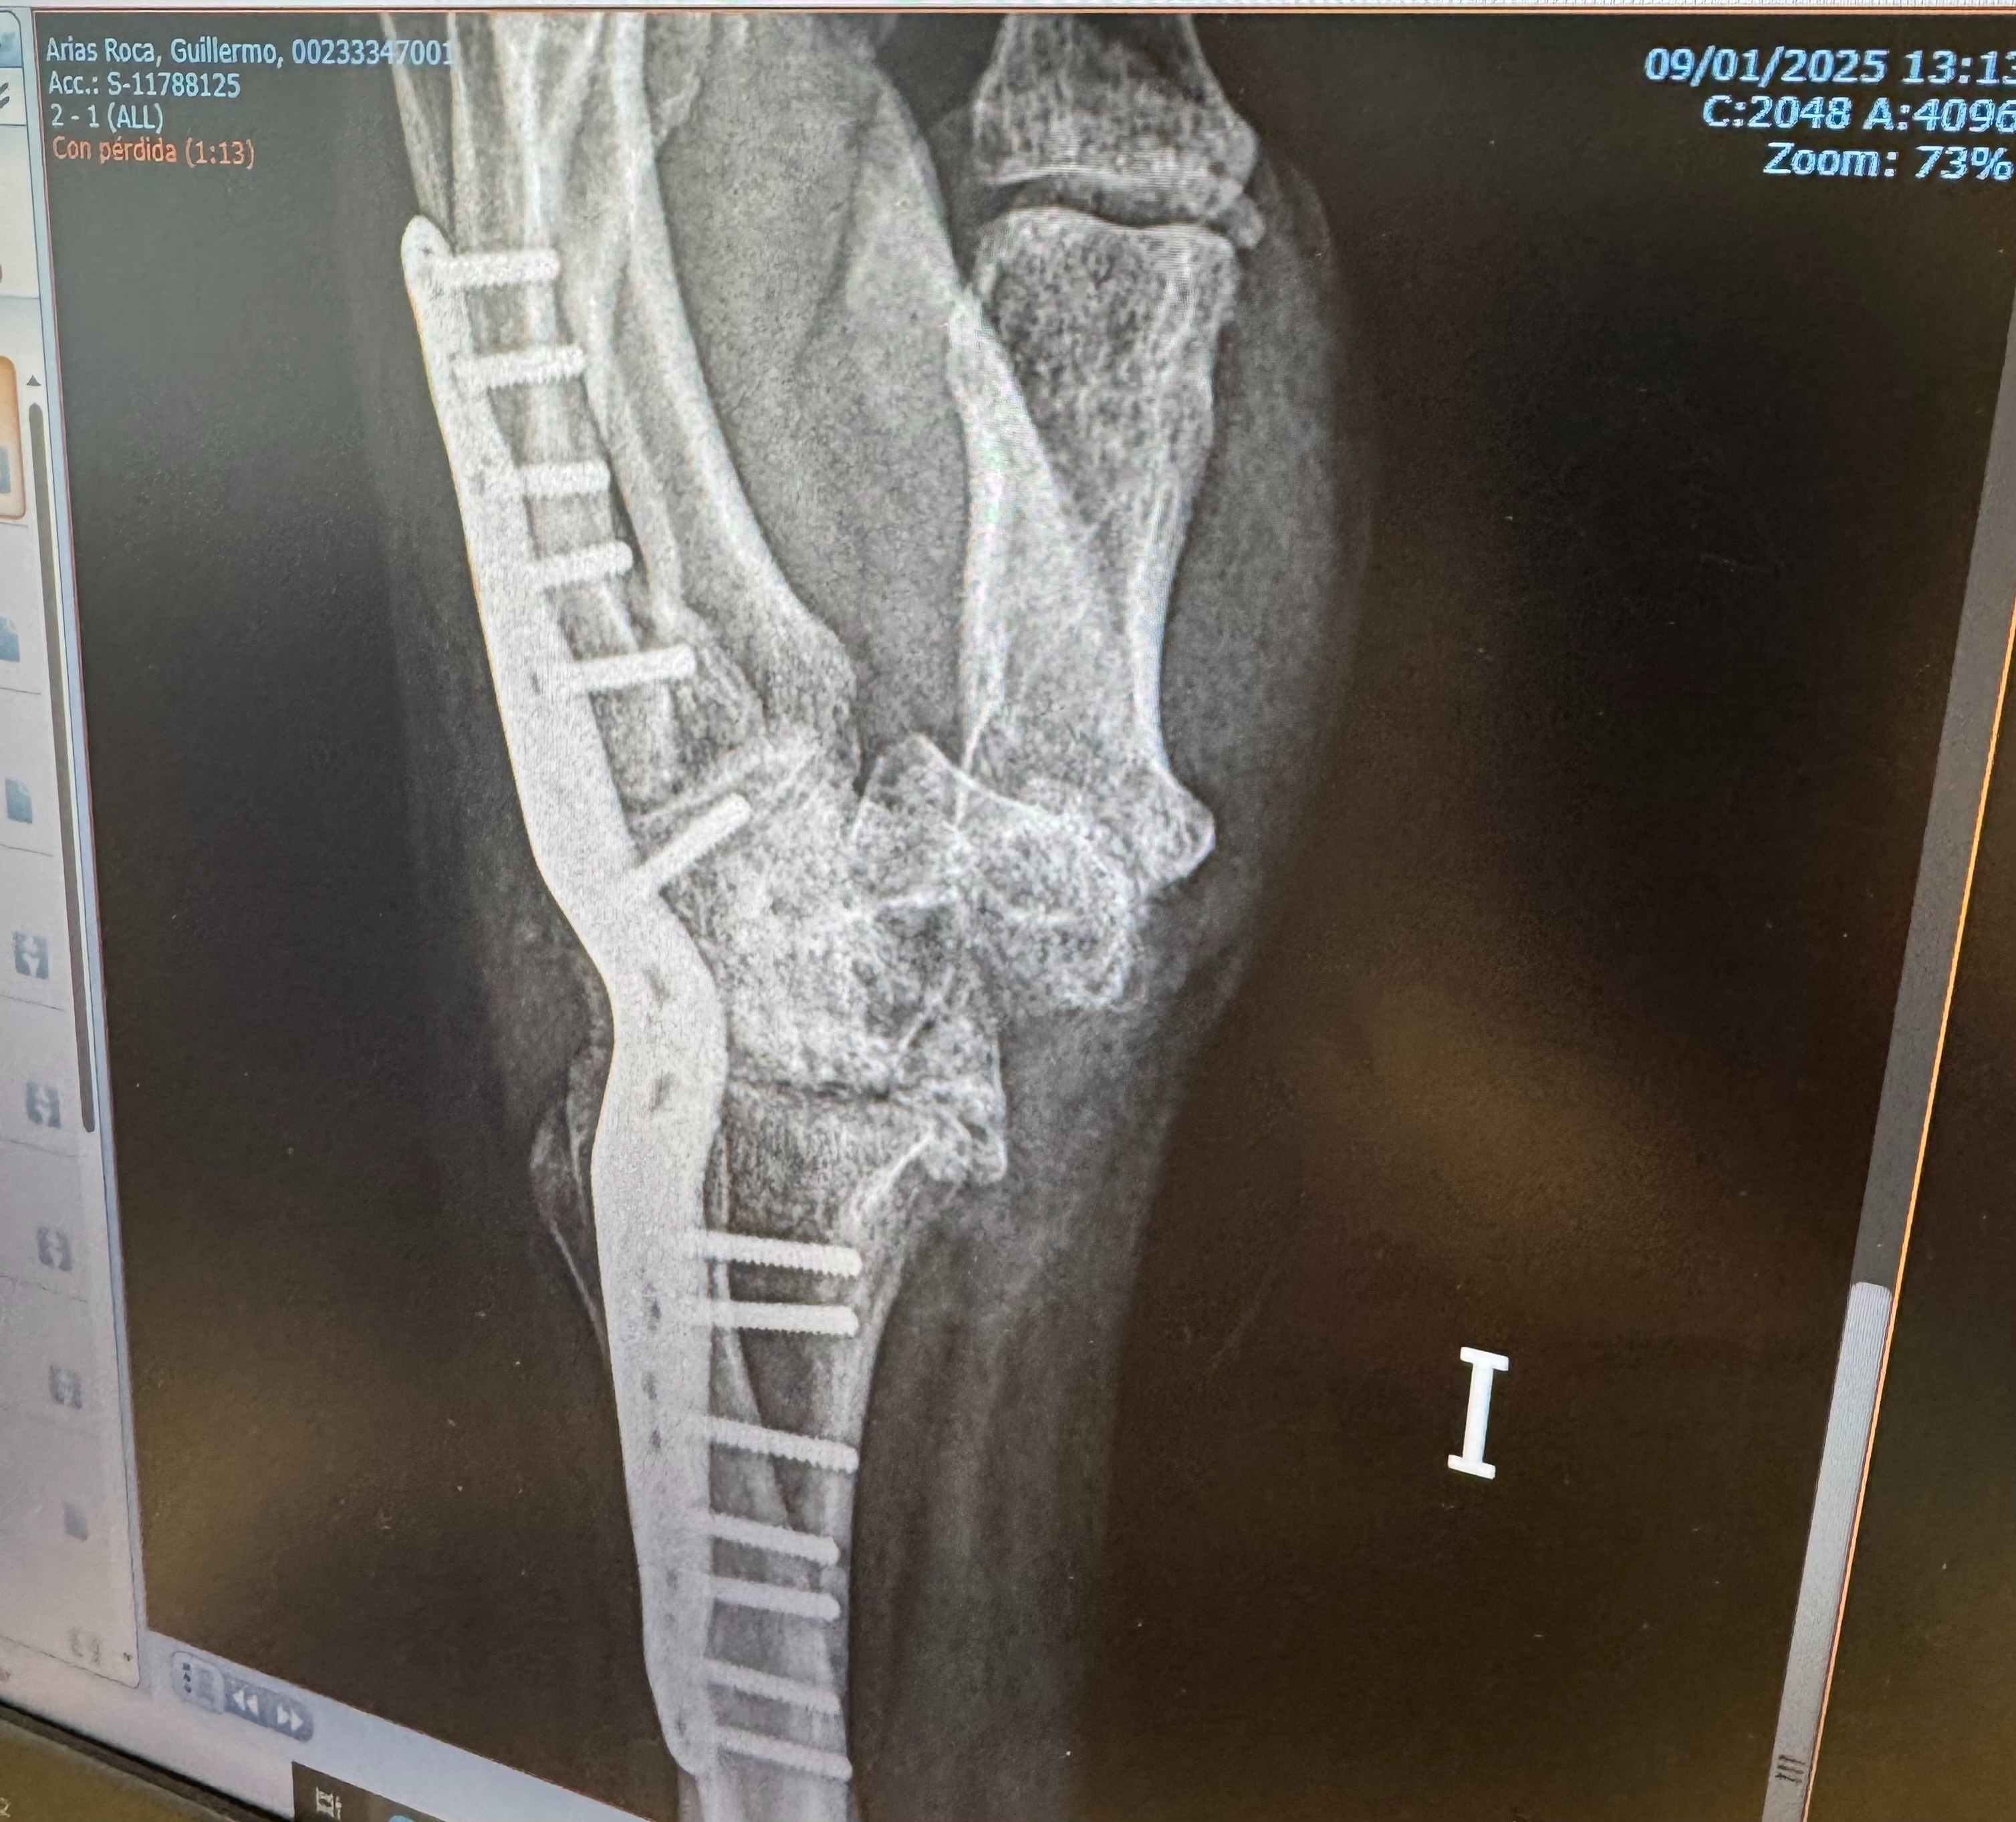

En marzo de 2024, decidido a terminar con mi vida, un amigo me convenció de ver a un especialista. Ahí descubrieron que llevaba 31 años con la muñeca rota: una simple operación resolvía gran parte del problema. La pregunta es inevitable: ¿cómo nadie lo vio antes? ¿Cómo se permitió tanto encubrimiento, soborno y abandono?